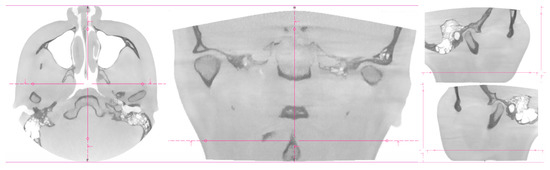

2. Patients, Materials, and Methods

3. Results